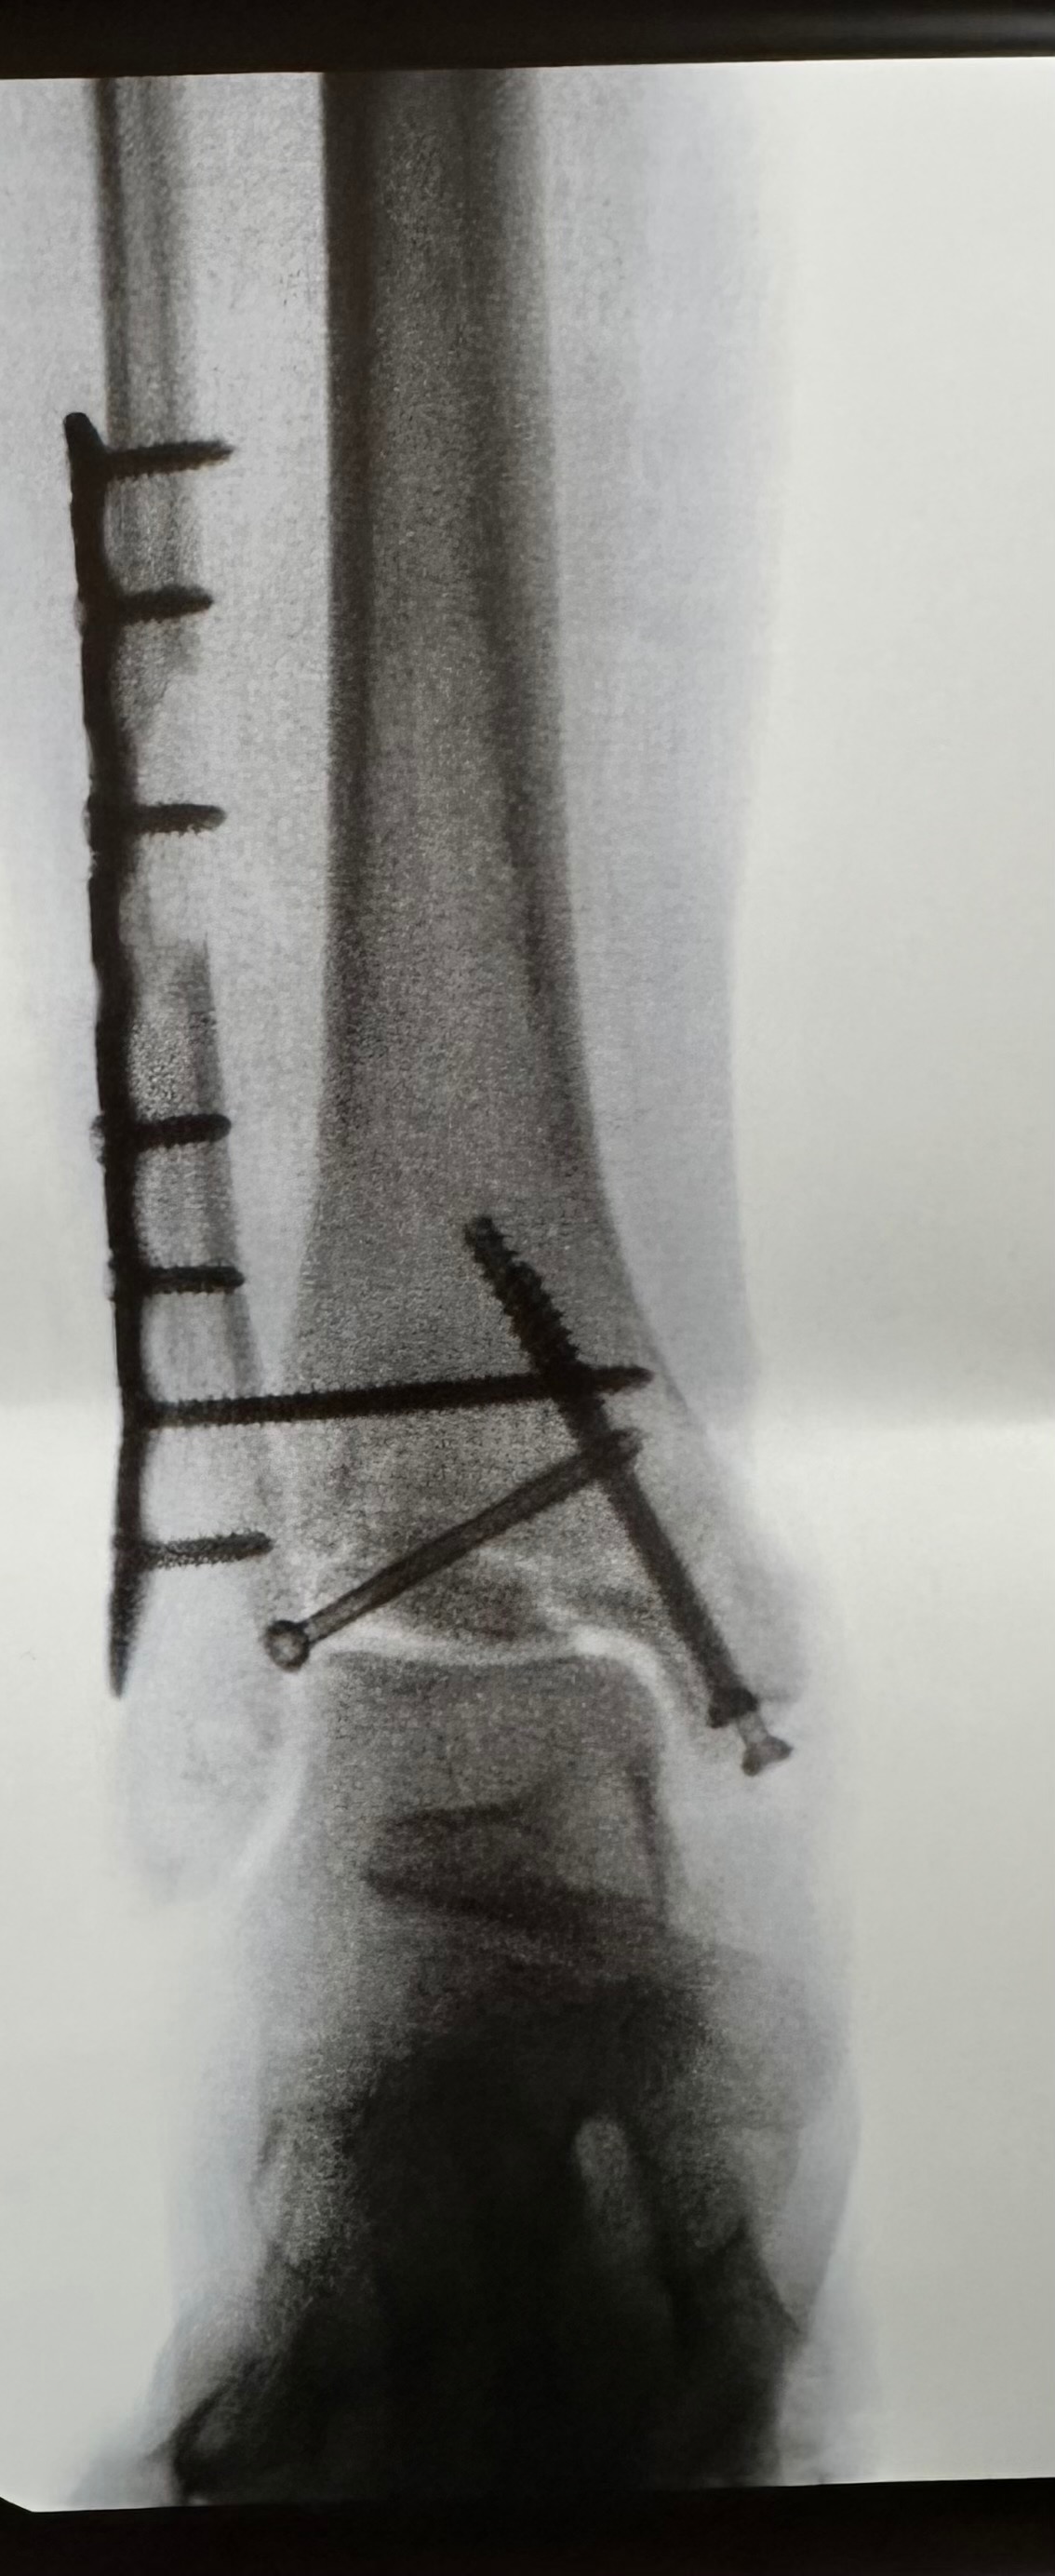

Hi, I’m Marianne McDonald, Annica’s (Annie) mom. On Sunday, June first, Annie was in a life-changing car accident. She was lucky to walk away with her life, and we are very grateful God had more for her to do in life. Annie suffered serious damage to her right leg. They were able to save her foot, but she cannot even put weight on it for 8 weeks. Her left ankle is also broken. Due to the trauma and mostly being bedridden for some time, she is on blood thinners to reduce the risk of stroke and pulmonary embolisms, which are life-threatening. Annie now requires round-the-clock care at home. I tried to have insurance in place to avoid having to ask for outside help, but unfortunately, her being disabled and needing at-home care from me wasn’t covered. I was eligible for leave from work, but it’s unpaid. We also have many medical bills outside of insurance coverage and other costs, including replacing my vehicle, that were unexpected to come all at once. As I eat my humble pie (this coming from a very independent woman), I ask for help so I can be home with her to care for her. Everyone’s support has been unfathomable so far. I appreciate each and every one of you, and so does Annica.